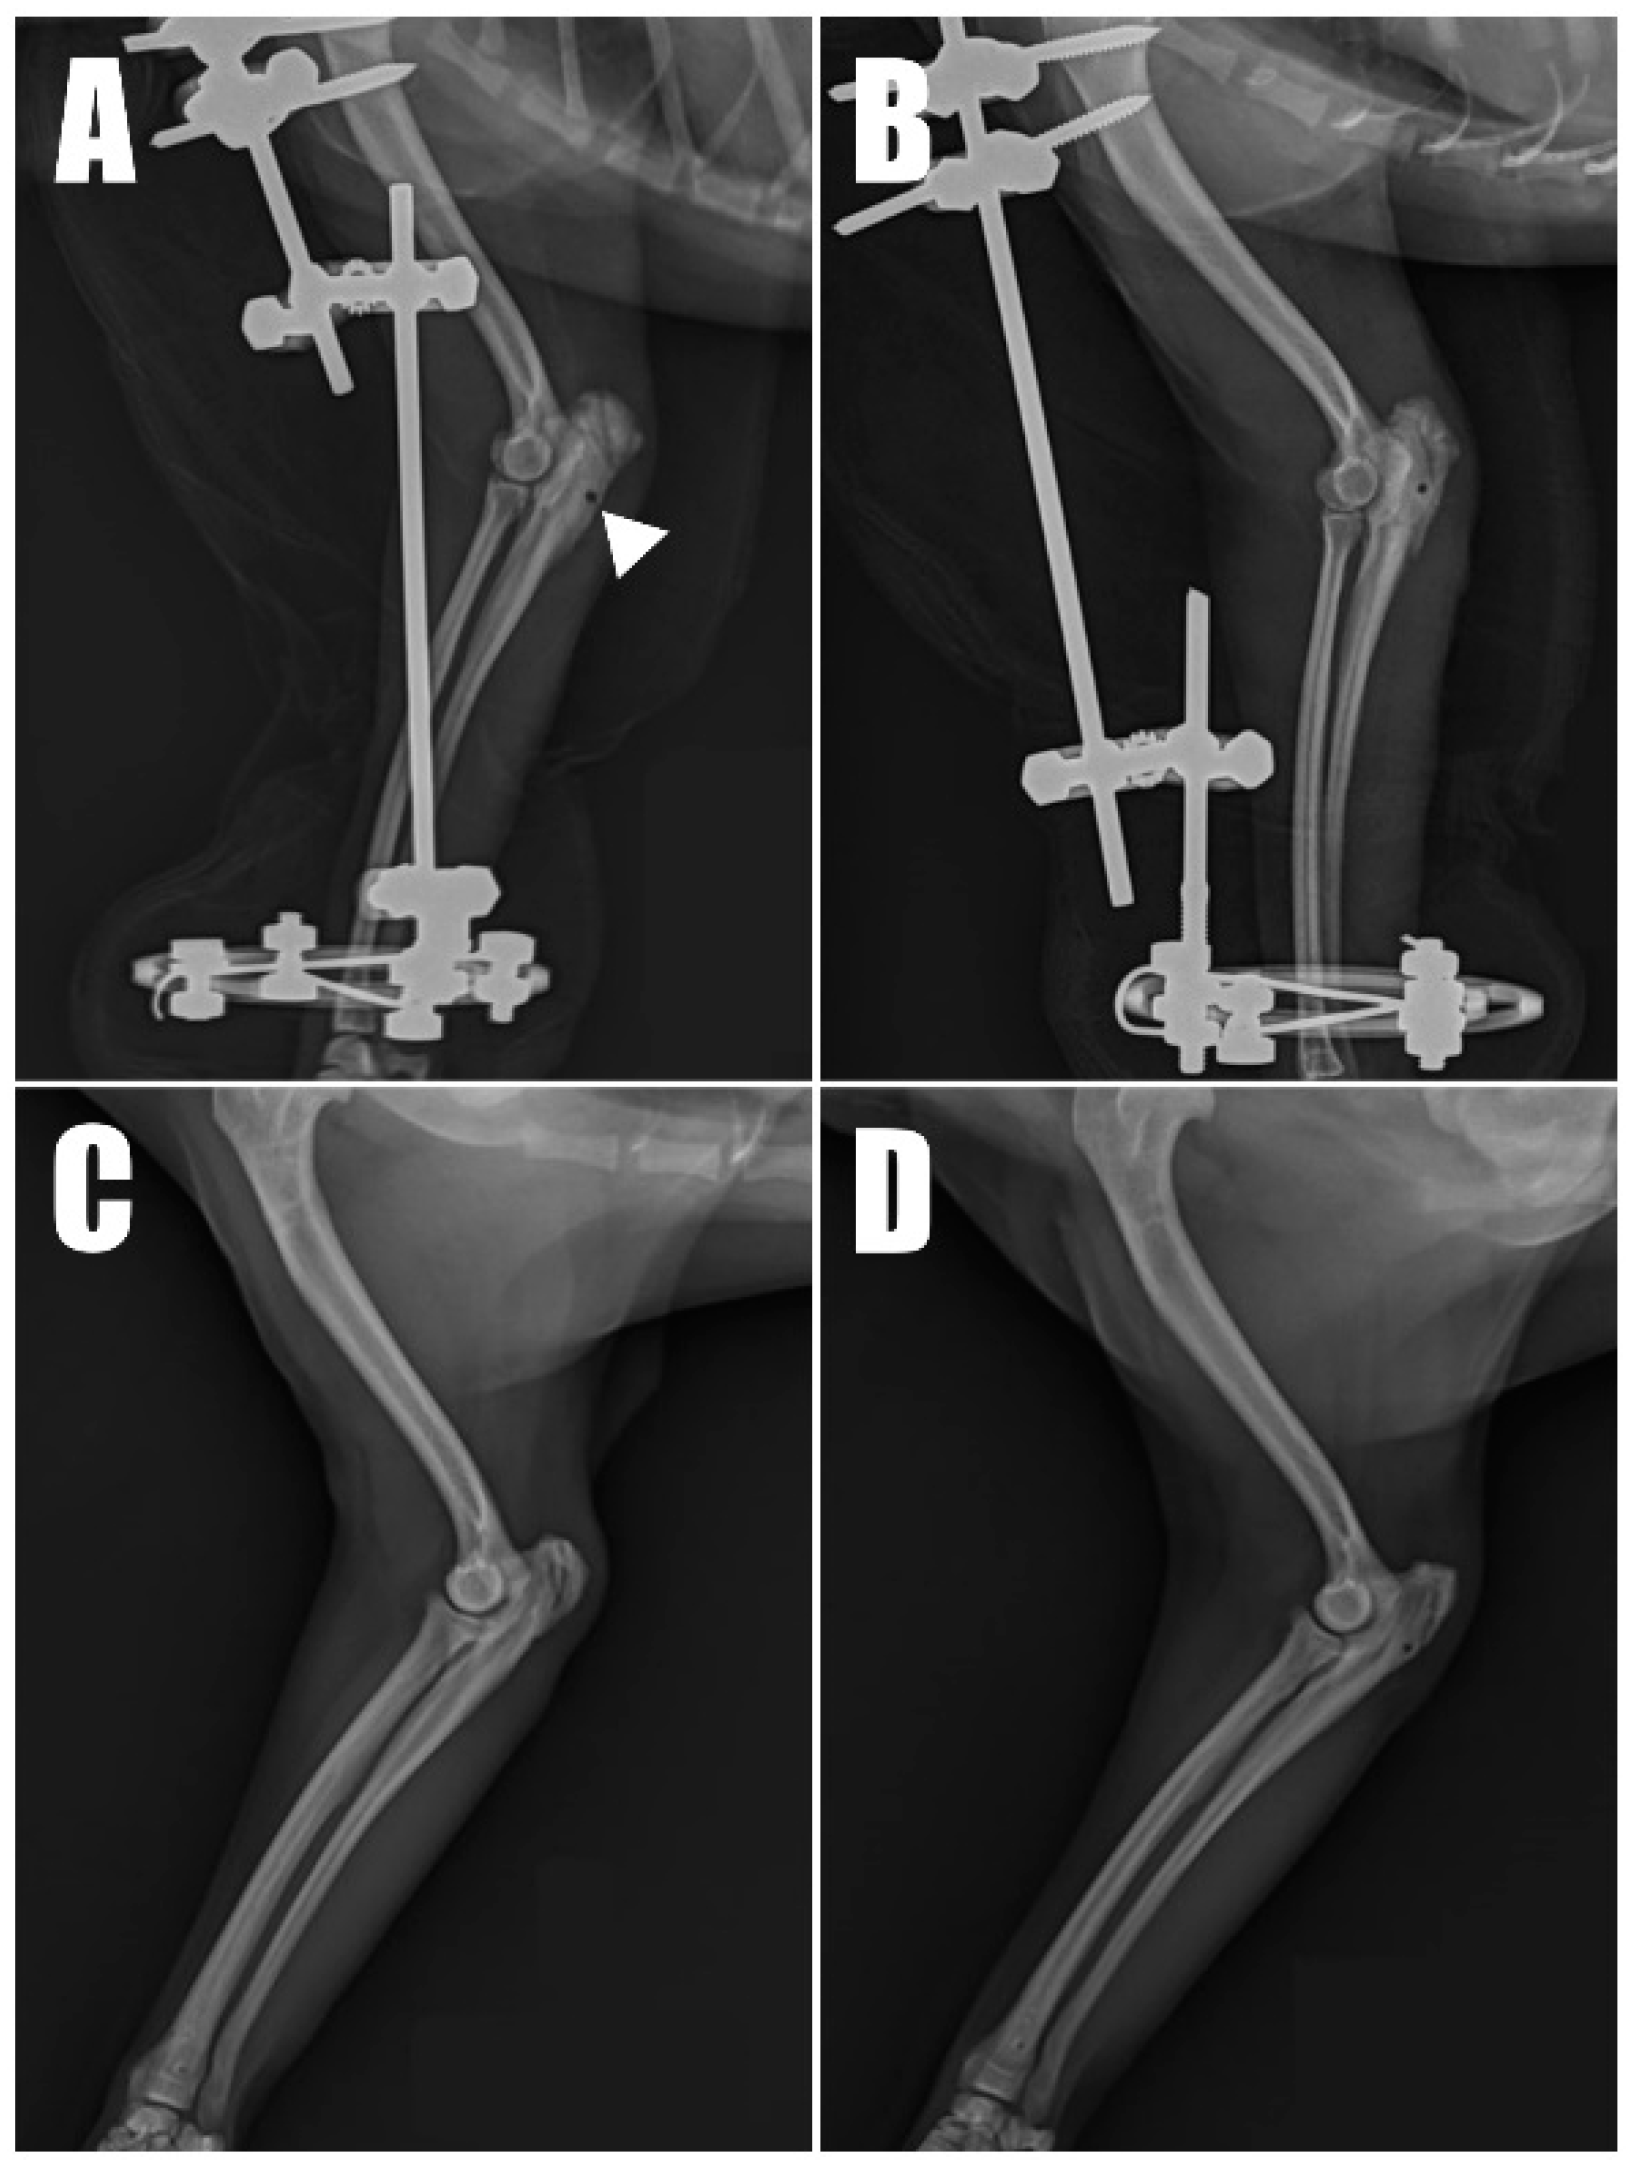

Figure 1B) as follows: four weeks in the left forelimb and three weeks in the right forelimb, each following a fall from a height. Physical examination revealed a pain response and nodular formation in the proximal region of the olecranon, with no extension response during the triceps brachii squeeze test. Radiographs revealed radiolucent opacities on both sides of the olecranon (

Figure 2A,B), and ultrasonography identified defects (

Saline lavage was performed on the surgical site, which was then swabbed for culture and sensitivity tests before routine closure. Following closure, a trans-articular external skeletal fixator (TAESF) was applied for joint immobilization. A circular ring was placed on the radius using two 1.0 mm K-wires. Two 2.4 mm Duraface ESF end thread pins (IMEX Veterinary InC., Longview, TX, USA) were inserted into the humerus and connected with lateral connecting bars. The elbow joint angle was immobilized at 150 degrees to reduce tension on the tenorrhaphy. The contralateral limb underwent identical treatment.

Postoperative radiographs and ultrasound images (

Figure 6) were taken to confirm the position and connectivity (

Figure 7) of the tendon on the olecranon. On the right side (

Figure 6A), the transverse hole was observed to be close to the caudal cortex, while the remaining bone tunnels were confirmed to have been drilled as intended. For analgesia, remifentanil was continued for three days postoperatively at 0.1~0.3 ug/kg/min with constant rate infusion. The other postoperative therapy including antibiotics (amoxicillin and clavulanic acid, 12.5 mg/kg BID, for 14 days/Clindamycin, 11 mg/kg BID, for 14 days), NSAID (meloxicam, 0.1 mg/kg SID for 14 days), and gastrointestinal protectant (esomeprazole, 1 mg/kg SID for 14 days) were administered.

Immediate postoperative weight-bearing was observed. The patient was discharged two weeks postoperatively with instructions for cage rest. To prevent joint ankylosis, the bolts and nuts were slightly loosened, and the trans-articular external skeletal fixator (TAESF) was progressively released six weeks postoperatively to allow a limited range of motion of about 10 degrees. The range of motion (ROM) was gradually increased to a maximum of 30 degrees, and ultimately, the TAESF was removed nine weeks postoperatively. The limbs were then supported in a Spica splint for an additional two weeks.

Radiography (

Figure 6C,D) and ultrasonography (